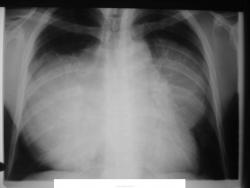

Мужчина 36 лет, рентгеногафия и КТ грудной полости.

Жалобы на субфебрильную температуру, боли в грудной клетке справа, слабость, похудание. ФГ 10 месяцев назад - норма.

Интенсивное, однородное затемнение в средних отделах справа, слева норма - мною был заподозрен м/долевой плеврит, пациент был направлен в областной центр торакальной хирургии. Затем онкодиспансер, затем институт рака в Киеве. Результат гистологии тератобластома средостения. 2 курса химиотерапии контрольное КТ в октябре - отрицательная динамика.

Р-графия от 30.11.09

В начале 2010 года пациент умер.